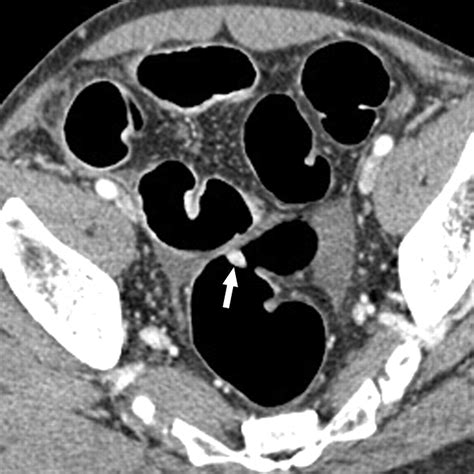

At its core, Ct Scan Colonography is a specialized radiological imaging test that produces 2D and 3D images of the large intestine. Unlike a standard colonoscopy, which involves physical exploration of the bowel, this procedure relies on computed tomography (CT) to create a detailed internal map. The process requires the patient’s colon to be inflated with air or carbon dioxide to ensure the walls of the bowel are fully distended, which allows the CT scanner to capture clear, unobstructed views of the lining.

However, it is important to acknowledge the limitations. The most notable limitation is that while the scan can identify suspicious polyps, it cannot remove them. If a polyp is detected during the scan, the patient will need to undergo a traditional colonoscopy to biopsy or remove the growth. Furthermore, because the scan utilizes ionizing radiation, it is generally recommended to discuss the cumulative exposure with a healthcare provider, especially if frequent screenings are anticipated over a lifetime.